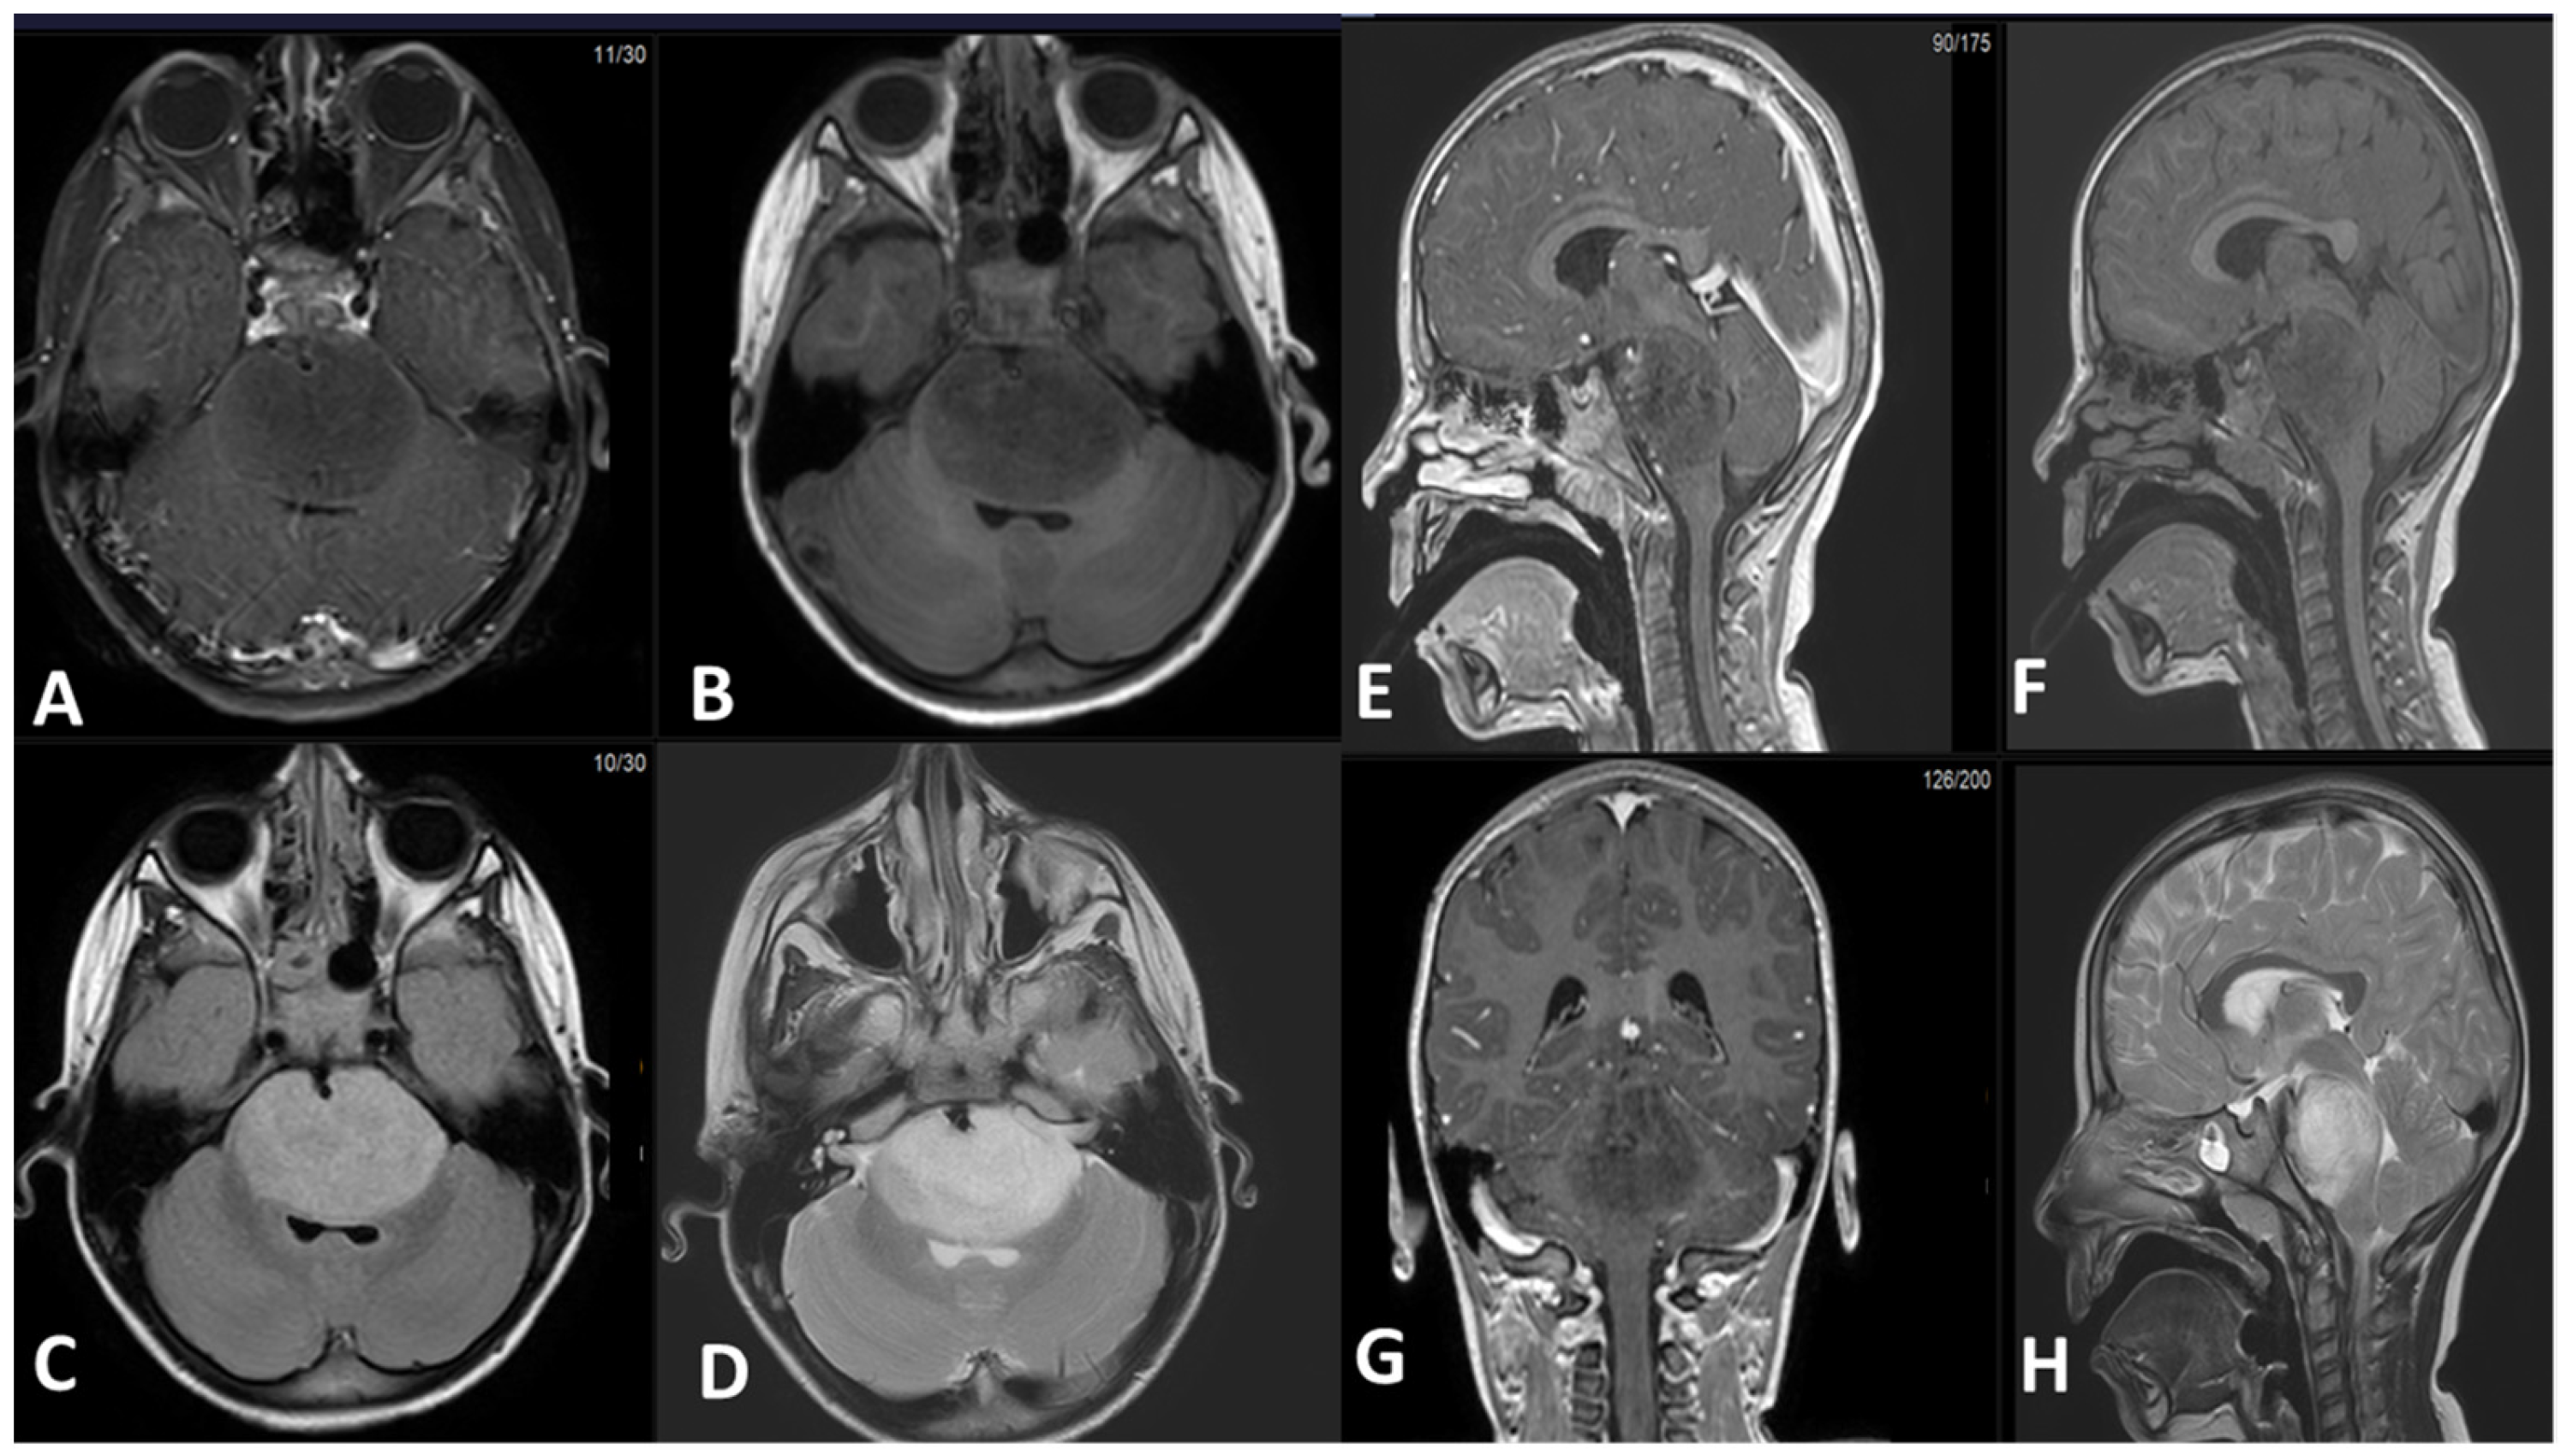

5.1. Magnetic Resonance Imaging (MRI):